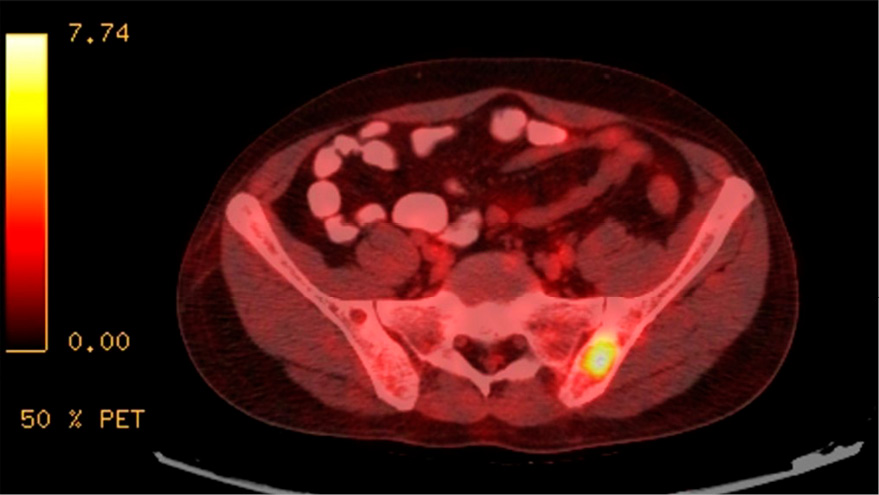

Se realizó una tomografía por emisión de positrones con 18F-FDG (PET/TC). Las imágenes de cabeza y cuello revelaron una glándula paratiroides izquierda aumentada de tamaño, posterior e inferior al lóbulo tiroideo izquierdo, de 15×16 mm (SUV máx. <1). En el tórax, se observó una consolidación en el lóbulo superior izquierdo de 19×10 mm (SUV máx. 1,5), con ganglios linfáticos mediastinales calcificados. En el sistema musculoesquelético, se halló una lesión lítica en la espina ilíaca posterosuperior izquierda (SUV máx. 7,8) y múltiples lesiones permeativas vertebrales lumbares. No se detectaron otras lesiones metabólicamente activas (Figura 3).

Figura 3.

Una tomografía por emisión de positrones (PET/TC) con 18F-FDG que muestra una lesión lítica en la espina ilíaca posterosuperior izquierda con un SUV máximo de 7,8.